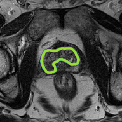

Despite their outstanding accuracy, semi-supervised segmentation methods based on deep neural networks can still yield predictions that are considered anatomically impossible by clinicians, for instance, containing holes or disconnected regions. To solve this problem, we present a Context-aware Virtual Adversarial Training (CaVAT) method for generating anatomically plausible segmentation. Unlike approaches focusing solely on accuracy, our method also considers complex topological constraints like connectivity which cannot be easily modeled in a differentiable loss function. We use adversarial training to generate examples violating the constraints, so the network can learn to avoid making such incorrect predictions on new examples, and employ the Reinforce algorithm to handle non-differentiable segmentation constraints. The proposed method offers a generic and efficient way to add any constraint on top of any segmentation network. Experiments on two clinically-relevant datasets show our method to produce segmentations that are both accurate and anatomically-plausible in terms of region connectivity.